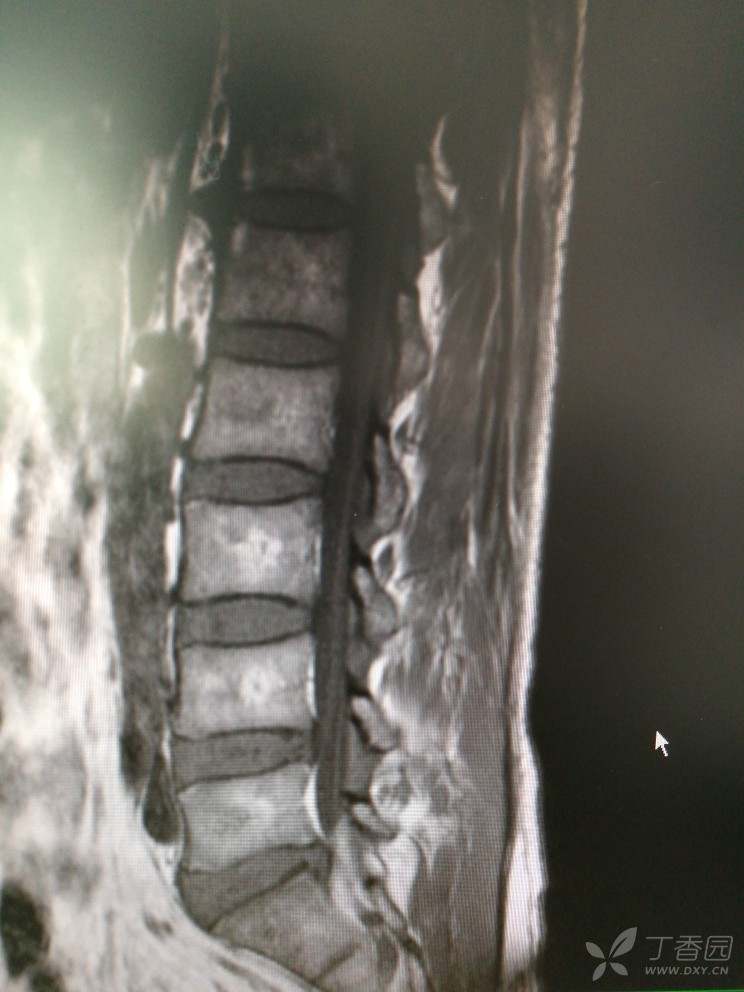

双下肢麻木查因

患者男,46岁,双下肢麻木2年余。

2年前无明显诱因出现双下肢麻木,双下肢沉重感,感觉对称,在坐位、平卧位时发生,活动或抬高下肢后缓解,无双下肢放射痛及乏力等。

查体:腰椎活动可,腰肌稍紧,L2-S1椎无明显压痛,双侧坐骨行程无压痛,直腿抬高试验(-),加强试验(-)肌力5级,肌张力正常,生理反射存在,病理反射未引出。

入院查MRI

我想问还是考虑L4/5 L5/S1椎间盘的变性引起的吗?